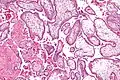

Micrograph showing chorionic villi. Intermediate magnification. H&E stain.

Chorionic villi are villi that sprout from the chorion to provide maximal contact area with maternal blood.

They are an essential element in pregnancy from a histomorphologic perspective, and are, by definition, a product of conception. Branches of the umbilical arteries carry embryonic blood to the villi. After circulating through the capillaries of the villi, blood returns to the embryo through the umbilical vein. Thus, villi are part of the border between maternal and fetal blood during pregnancy.

The bulk of the villi consist of connective tissues that contain blood vessels. Most of the cells in the connective tissue core of the villi are fibroblasts. Macrophages known as Hofbauer cells are also present.